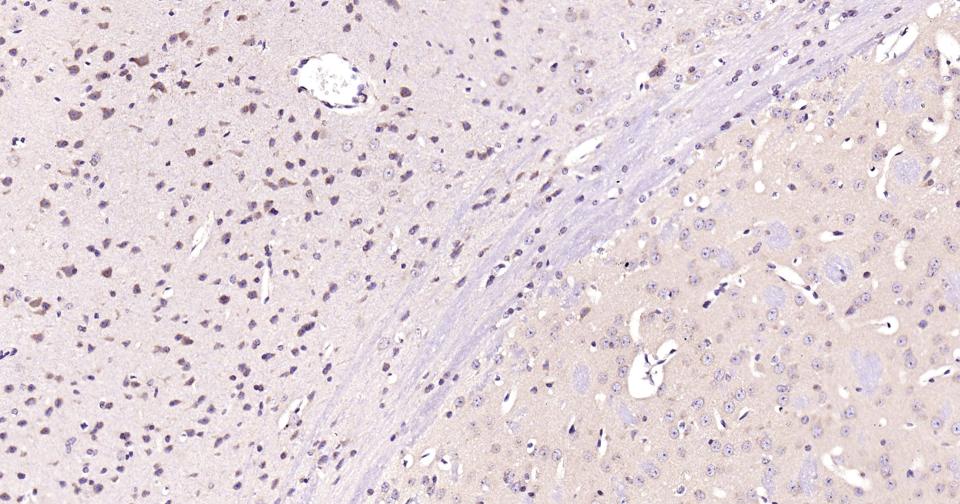

Paraformaldehyde-fixed, paraffin embedded Human Cerebrum; Antigen retrieval by boiling in sodium citrate buffer (pH6.0) for 15 min; Antibody incubation with TPH Monoclonal Antibody, Unconjugated(bsm-61227R) at 1:200 overnight at 4°C, followed by conjugation to the SP Kit (Rabbit, SP-0023) and DAB (C-0010) staining.